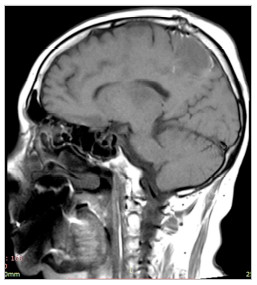

МРТ до операции

МРТ головного мозга после операции

Первичную диагностику при заболевании обычно проводит врач-невролог или нейрохирург. Доктор собирает анамнез, оценивает неврологический статус пациента. При необходимости к обследованию привлекаются офтальмолог, отоларинголог, онколог. Из инструментальных исследований наиболее информативным считается МРТ головного (иногда и спинного) мозга, которое выполняется в трёх проекциях.

После окончания лечения пациенту рекомендуют проходить регулярные профилактические обследования. МРТ головы необходимо выполнять каждые 2 или 3 месяца в течение первых двух лет наблюдения. Затем исследования проводятся раз в полгода, на пятый год после операции можно перейти на режим исследования один раз в год.